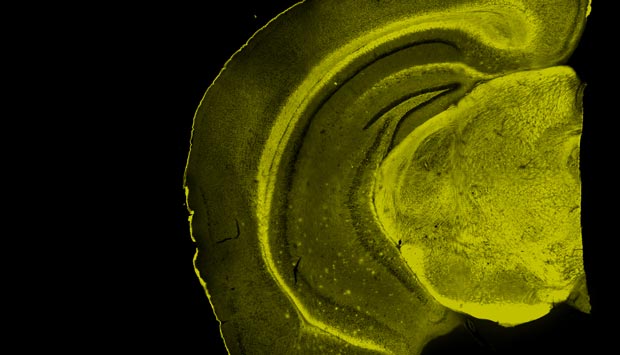

The fluorescent probe, BD-Oligo, developed by A*STAR detects amyloid-beta oligomers (yellow) in an Alzheimer’s disease-affected brain.

© 2016 A*STAR Singapore Bioimaging Consortium

After testing 3,500 DOFL compounds, they found BoDipy-Oligomer, known as ‘BD-Oligo’. This showed a stronger response to amyloid-beta oligomers, with the signal decreasing once a polymer started to form, which demonstrated to Chang and the team that they had found the first ever selective probe for oligomers.

With this fluorescent probe, the team was able to monitor oligomers in real time during the formation of fibrils. Additionally, in vivo tests on live mice revealed that BD-Oligo was able to cross the blood-brain barrier without any apparent toxicity.